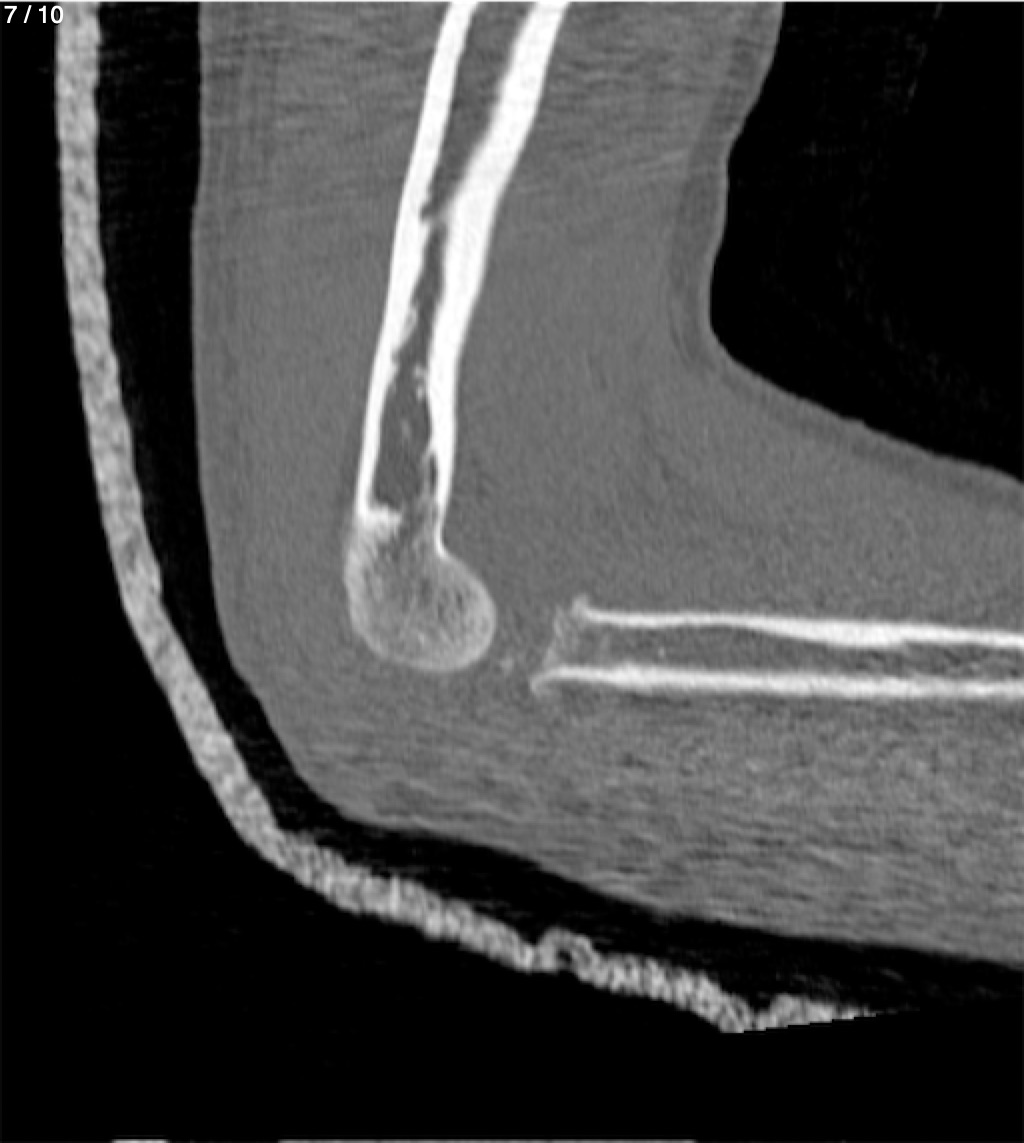

Antonio Dominguez Tino 21 A - Tac Codo Izq